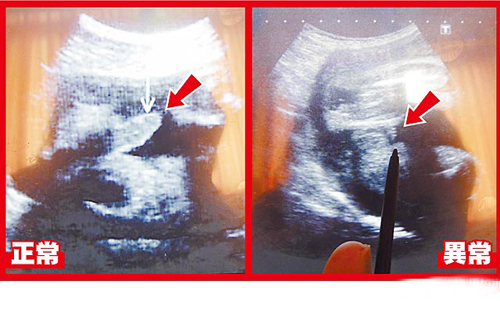

超声波可看到胎儿生殖器,左图箭头处为28周正常男婴生殖器:右图箭头处为异常男婴28周时生殖器画面。图片来源:台湾媒体

据报道,台中大里仁爱医院妇产科医师李瑞祺说,这名30岁产妇在怀孕28周时出现密集阵痛,医院紧急帮她安胎、进行超声波等检查,赫然发现胎儿生殖器特别短,阴囊还是空的,怀疑染色体或基因异常导致生殖器过短与隐睪症。但孕妇在26周时曾进行羊膜穿刺检查,显示性染色体正常。